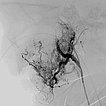

In der digitalen Subtraktionsangiographie (DSA) nach Injektion in die rechte Arteria carotis communis zeigt sich das Hämangiom wie erwartet vor allem aus der Arteria carotis externa versorgt.

Digitale Subtraktionsangiographie (DSA): Nach Einbringen transarteriell eines Führungskatheters 4F in die Arteria carotis externa und Vorbringen eines Mikrokatheters in die Arteria maxillaris. Das Hämangiom zeigt sich als typisches KM-Pooling (Tumorblush). Gut zu sehen auch der transvenös eingebrachte Ballon, der den venösen Abstrom ausblockt. Hier wird jetzt mit Partikeln der Größe 150 Mikron embolisiert ohne dass diese Partikel venös abströmen können.